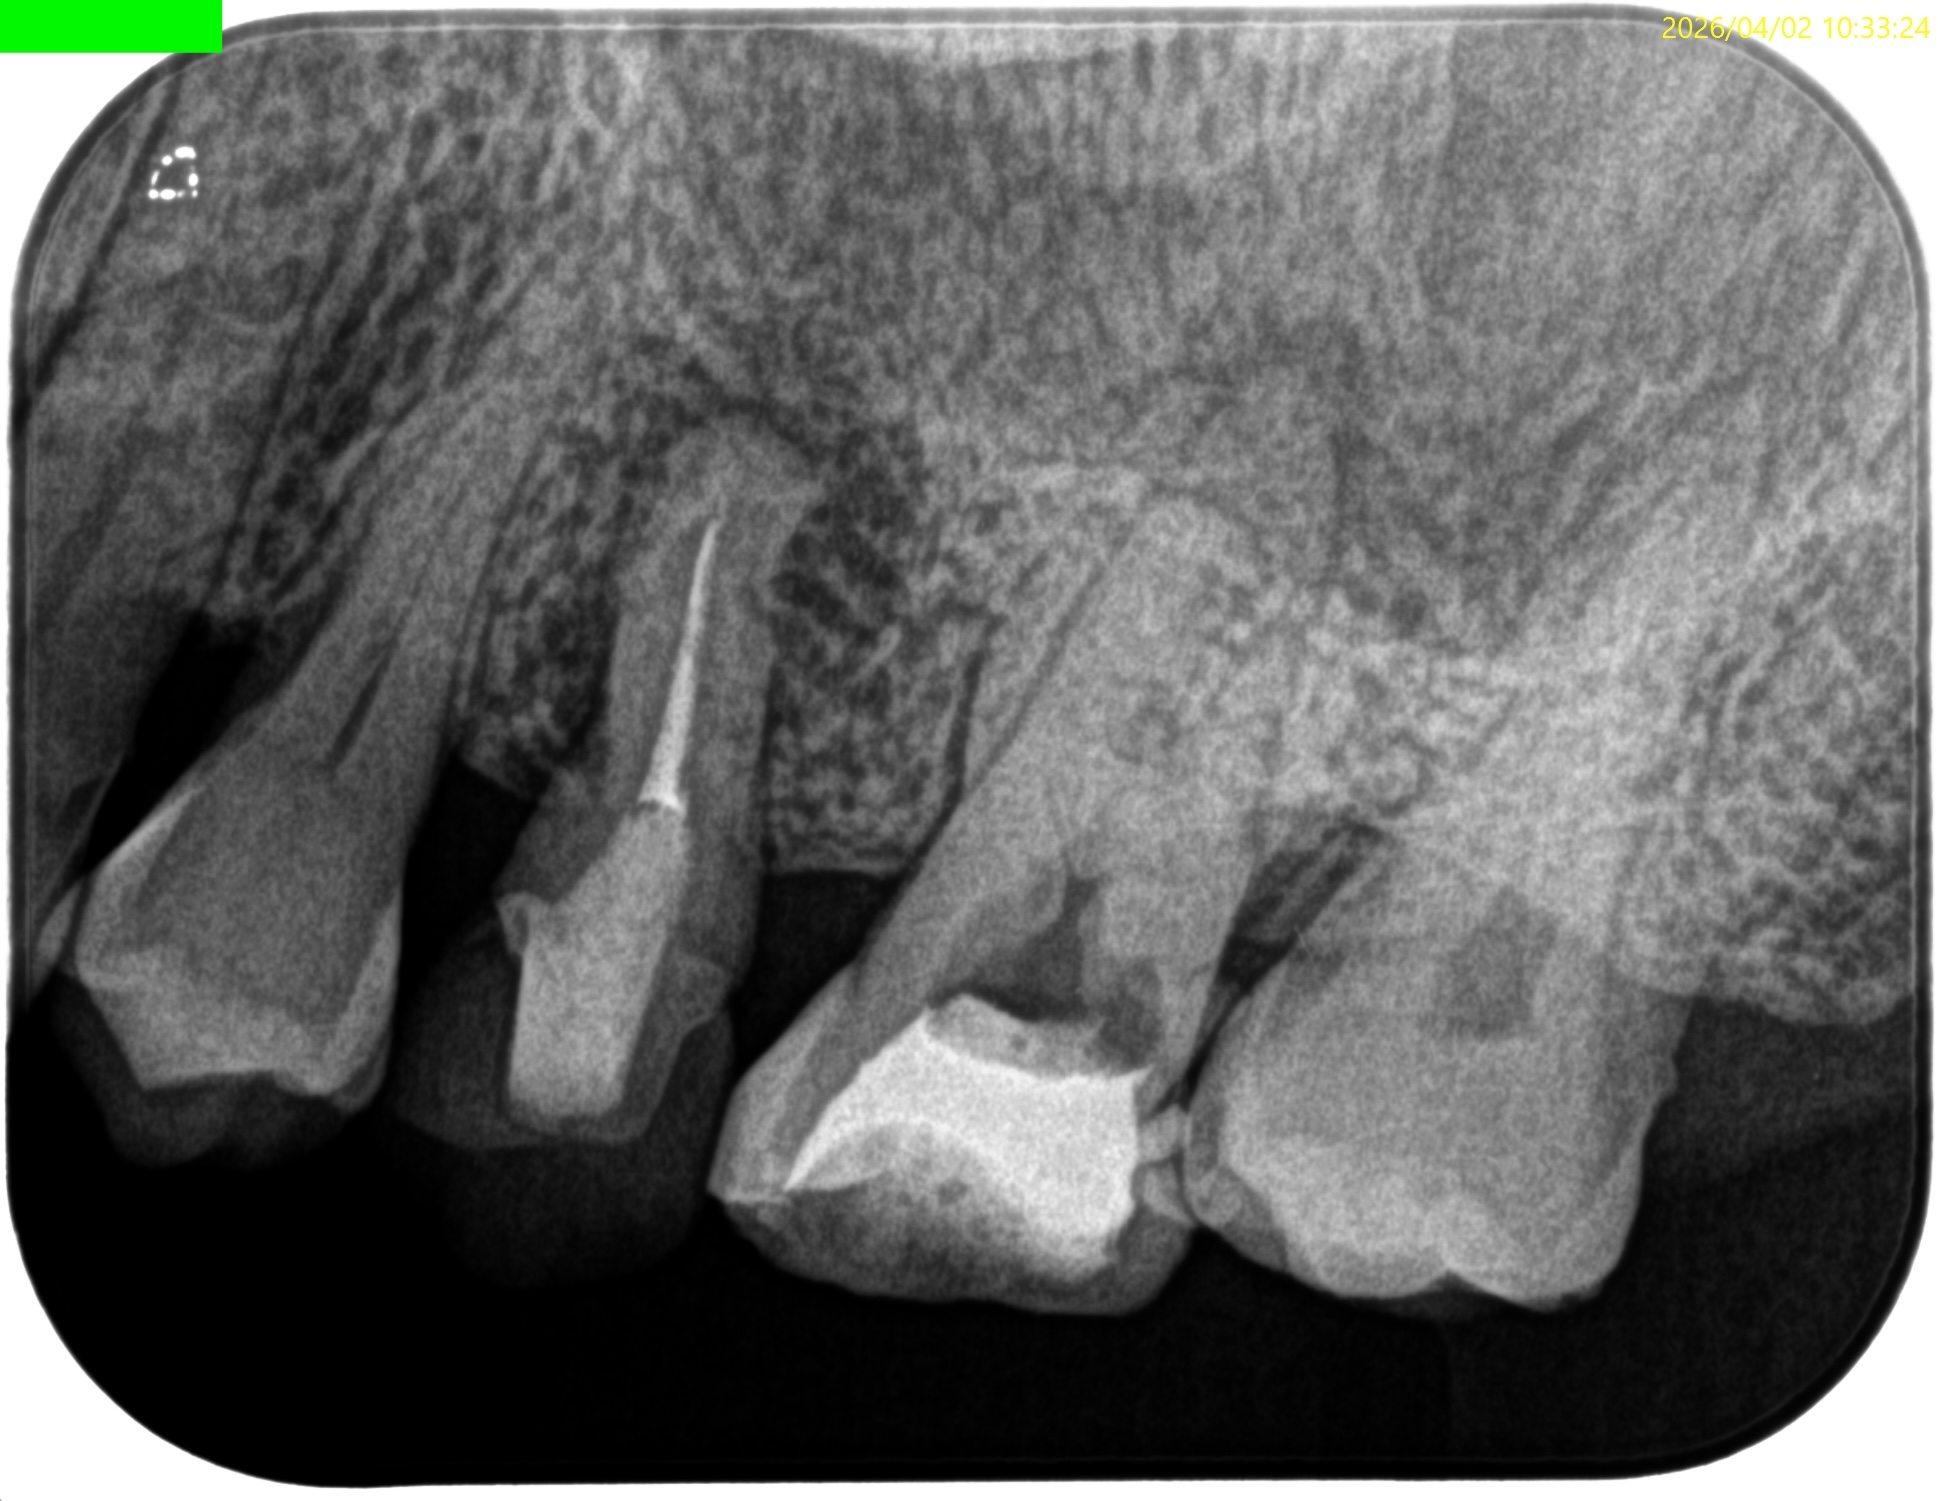

Pre-op Endo test(2026.4.2)

このPA2枚でみても、東京の歯科医院の担当者は根管口さえ発見していないという臨床的事実がわかる。

これは言葉は悪いがまさに…

手遊び

だ。

#14

MB

MB2

DB

P

B